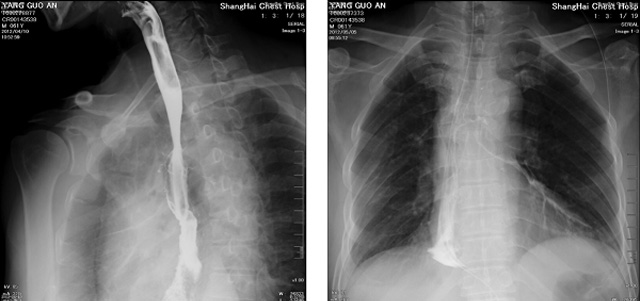

DR設(shè)備在2020年的新冠疫情中,加速了市場(chǎng)調(diào)整。以醫(yī)院為主的向二三級(jí)市場(chǎng)轉(zhuǎn)變。特別是小巧靈活的移動(dòng)DR設(shè)計(jì),填補(bǔ)CT和磁共振不能三維檢查的缺點(diǎn),滿足內(nèi)科外科特別是骨科的影像診斷需求。還有懸吊DR設(shè)備CT斷層射線系統(tǒng)。使用錐束成像技術(shù)對(duì)整個(gè)脊柱和整個(gè)下肢進(jìn)行了體積三維掃描。無需使用對(duì)比劑,即可使用X射線呼吸功能標(biāo)測(cè)來模擬模擬氣流和血流,以評(píng)估患者的肺動(dòng)脈血栓。

數(shù)字化X線攝影依然是患者初篩的關(guān)鍵一環(huán)。靜態(tài)DR限制于探測(cè)器平臺(tái)。只能進(jìn)行簡(jiǎn)單普通的數(shù)字化影像檢查。胸部的疾病沒辦法篩查出微小的病灶。這樣導(dǎo)致DR慢慢的被CT跟磁共振代替。這樣造成了原來配套的數(shù)字化影像DR設(shè)備的 閑置。所以DR需要跟CT融合擴(kuò)大DR的檢查使用場(chǎng)景。為DR提高更多的市場(chǎng)價(jià)值。X射線技術(shù)的原始形式和面向未來的可能性打破了CT成像和DR成像掃描技術(shù)之間的限制。融合成像趨勢(shì)更加明顯,多峰成像趨勢(shì)發(fā)展更加迅速。